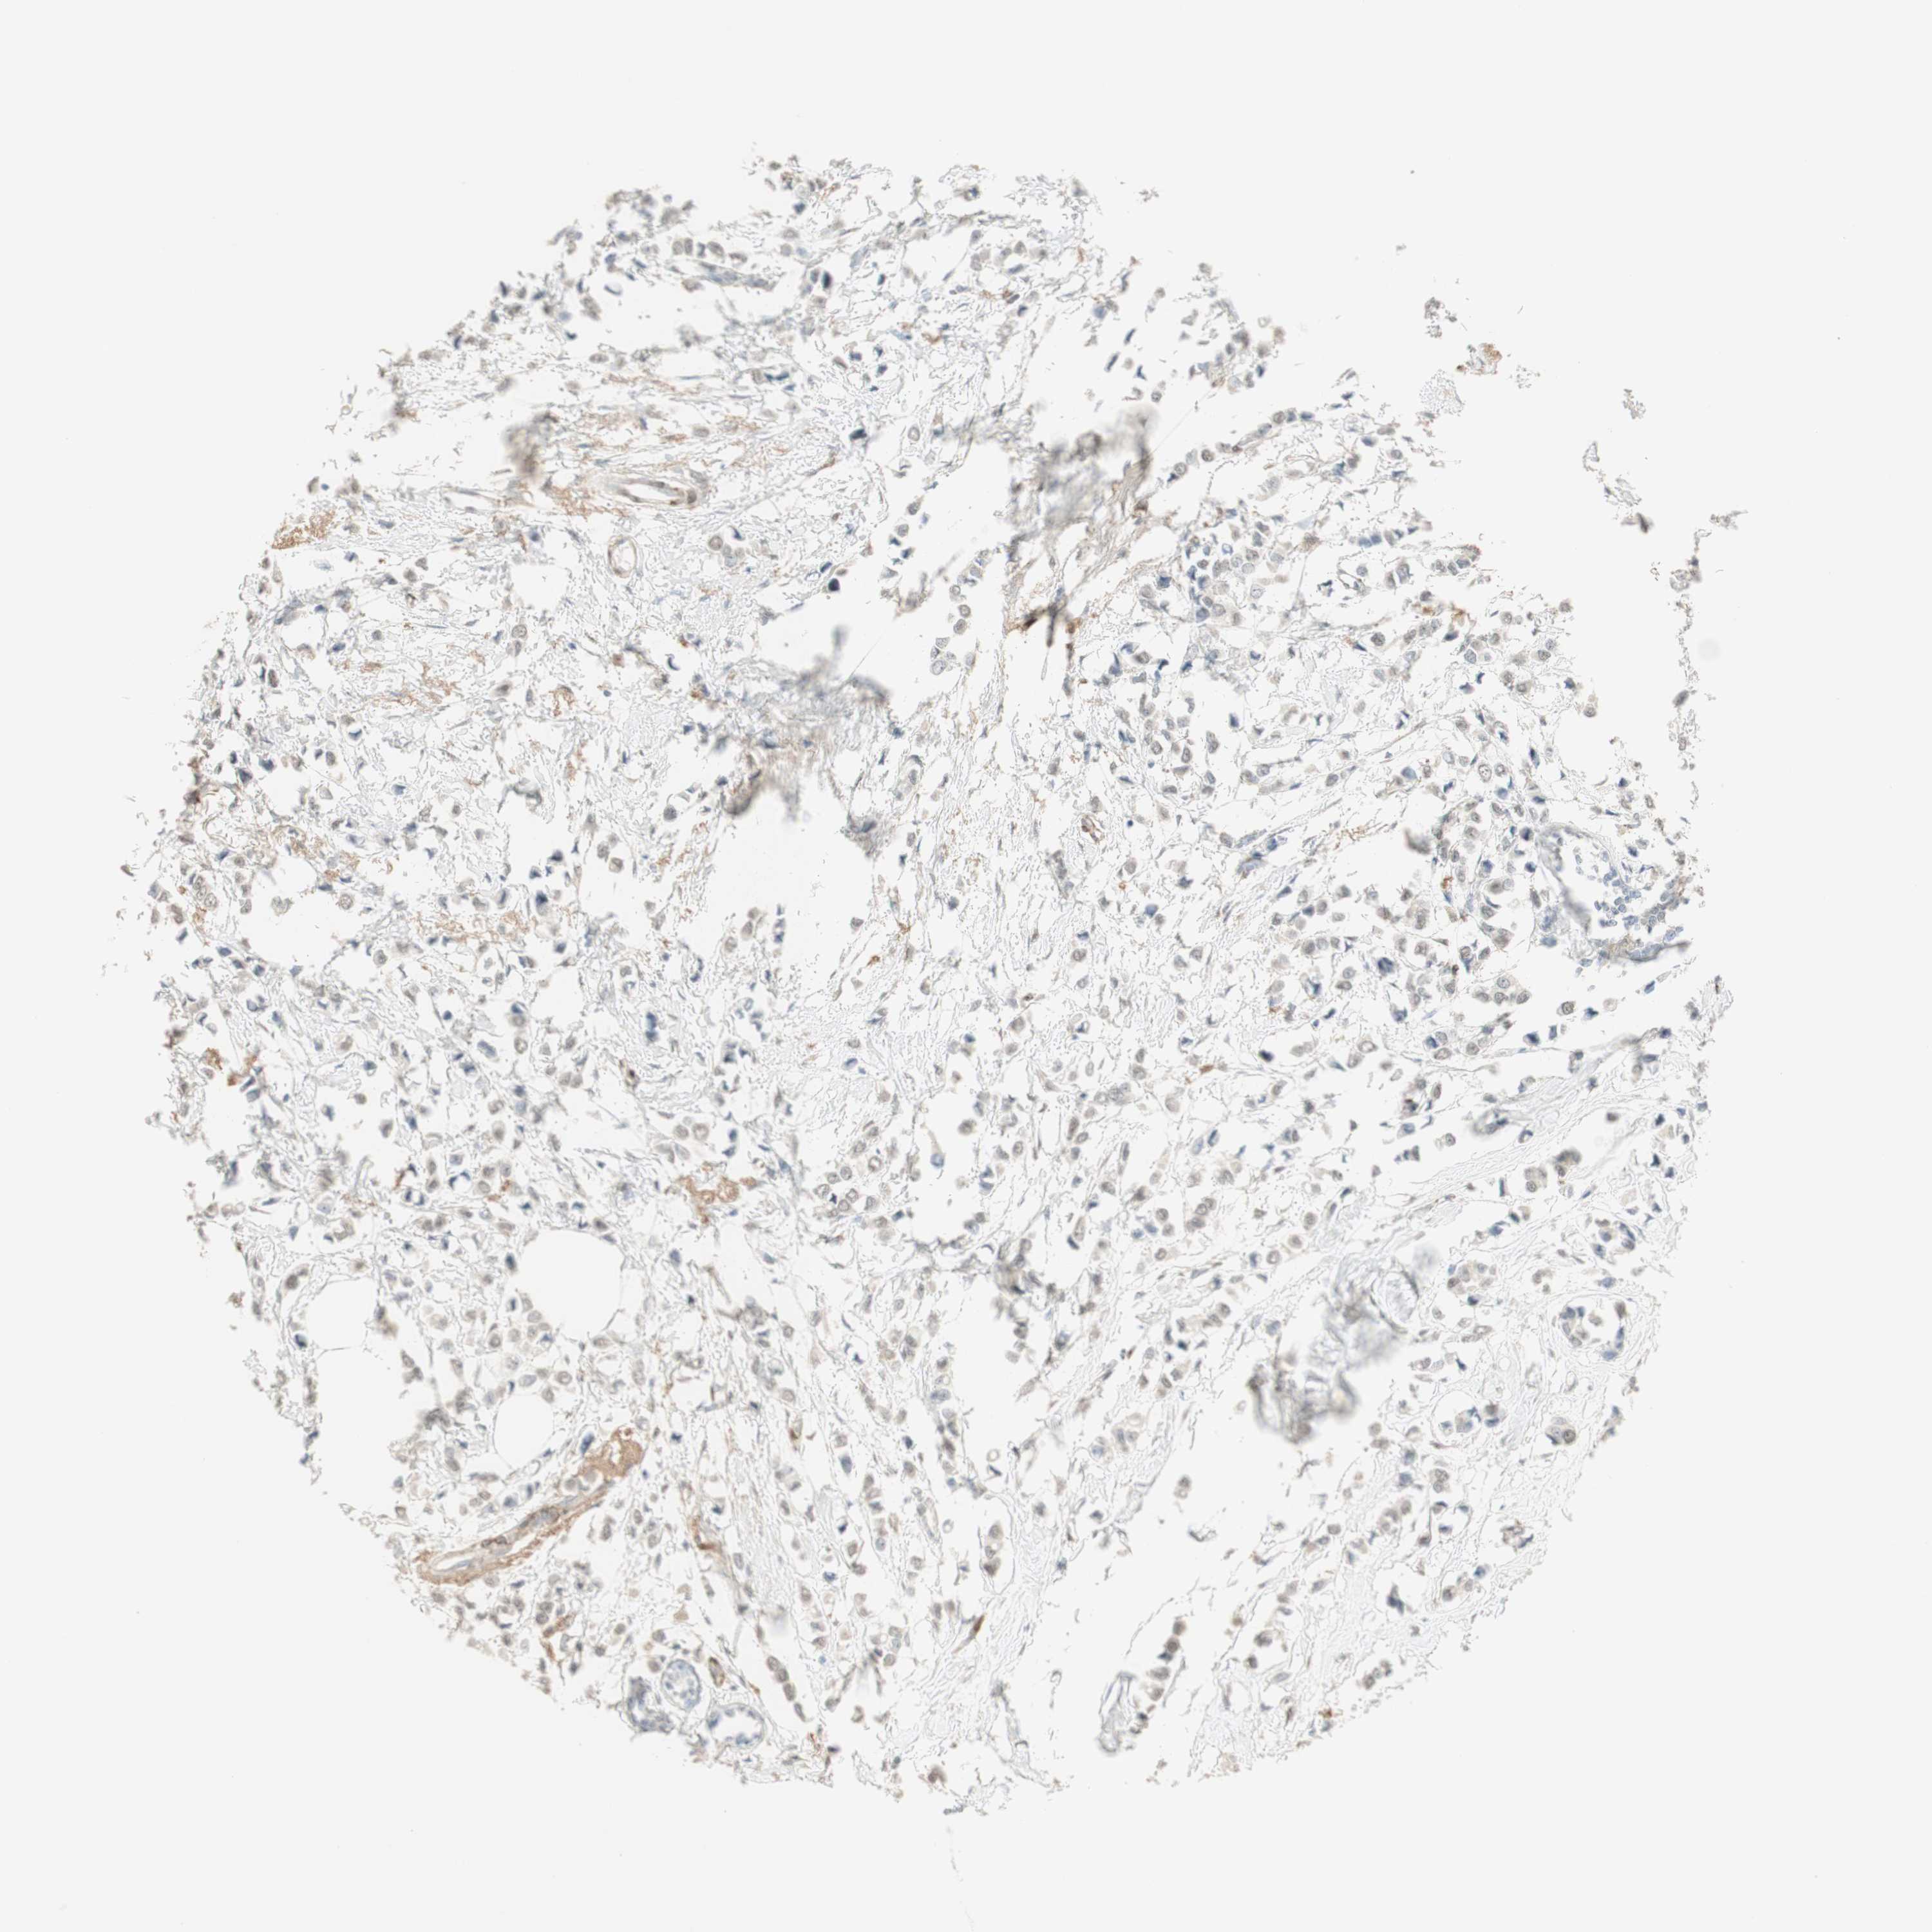

Breast cancer

Breast invasive carcinoma

MUC3A is not prognostic in Breast Invasive Carcinoma (TCGA)

Average pTPM 0.1

Number of samples 1022